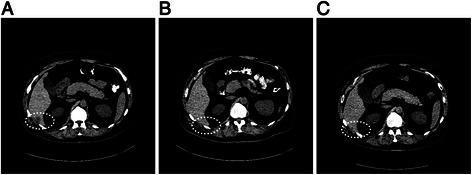

Three of the ten patients (median number of prior therapies = 2) attained prolonged CR (duration = 23.6+ to 28.7+ months); seven patients achieved either a PR or a short-lived CR. One patient who achieved CR ongoing at 28.7+ months and had tissue available close to the time of initiating BRAF inhibitor therapy had only a BRAF mutation. Abnormalities in addition to BRAF mutation found in other patients included: mutations in NRAS, APC and NF1; amplifications in BRAF, aurora kinase A, MYC, MITF and MET; deletions in CDKN2A/B and PAX5; and, alterations in RB1 and ATM. Heterogeneity between patients and molecular evolution within patients was noted.

10 例患者中的 3 例(既往治疗的中位数=2)获得了长期 CR(持续时间=23.6+至 28.7+个月);7 例患者达到 PR 或短期 CR。1 例在 28.7+个月时仍处于 CR 状态且在开始 BRAF 抑制剂治疗时附近有可用组织的患者仅存在 BRAF 突变。在其他患者中除 BRAF 突变外发现的异常包括:NRAS、APC 和 NF1 突变;BRAF、极光激酶 A、MYC、MITF 和 MET 扩增;CDKN2A/B 和 PAX5 缺失;以及 RB1 和 ATM 改变。注意到患者之间的异质性和患者体内的分子进化。